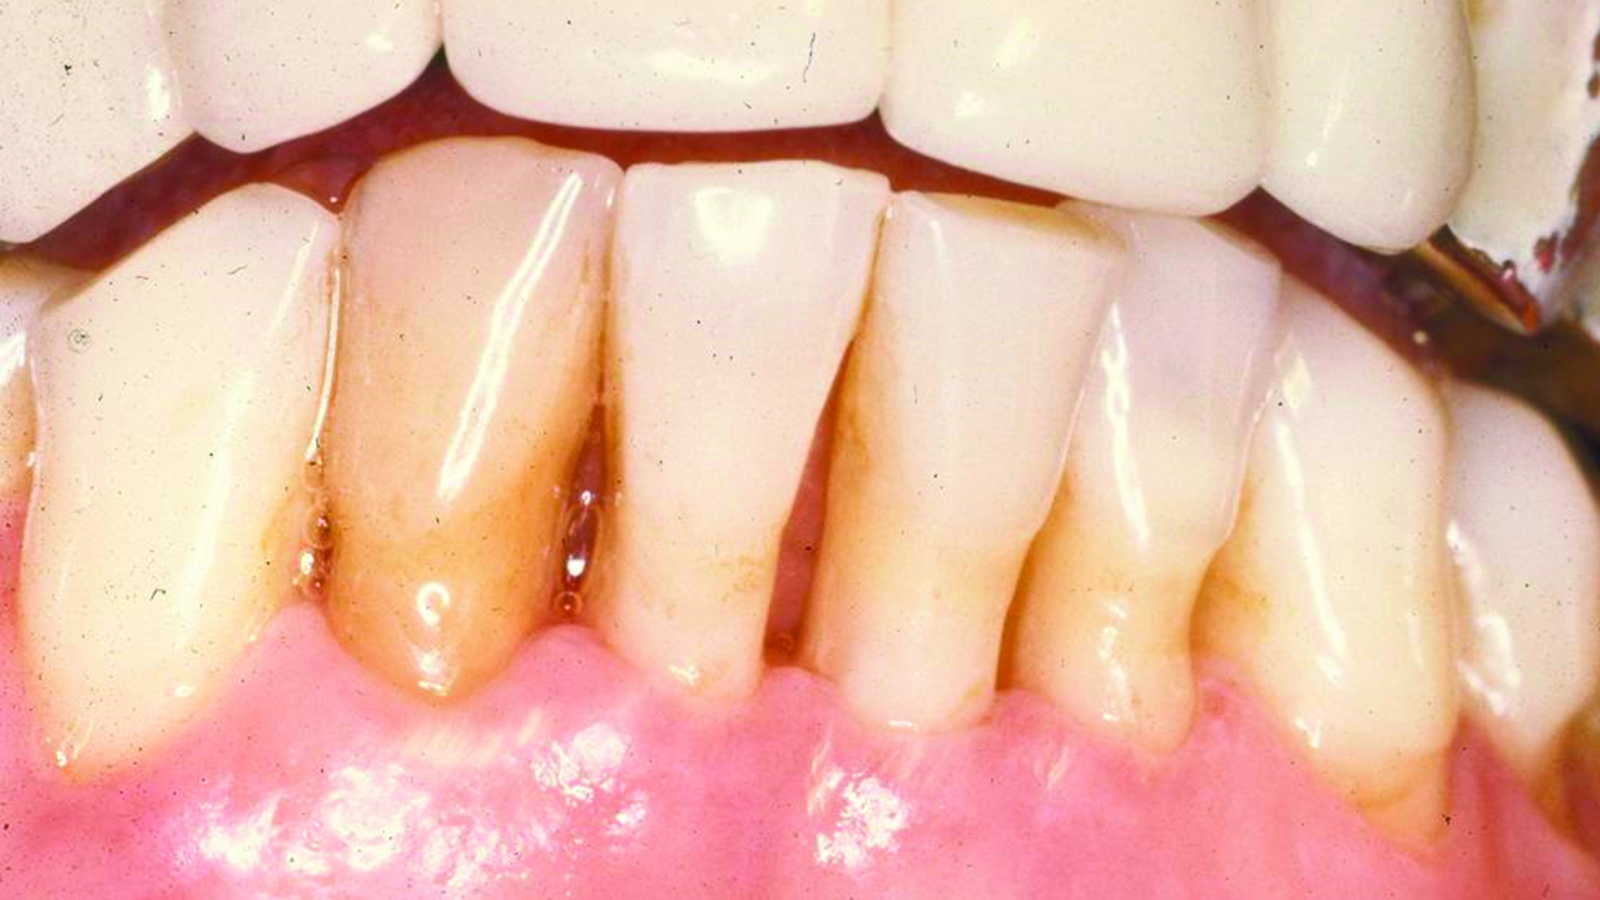

Fig 7. Case 2. Initial presentation of a patient with periodontitis (teeth Nos. 22 through 27). Generalized pocket depths of 6 mm to 7 mm were present, with wire splint on teeth Nos. 23 through 25.

Figure 7

Fig 8. Initial radiograph of the Case 2 patient, teeth Nos. 22 through 27. Fig 9. SRP resulted in the elimination of inflammation and remaining probing depths of 2 mm to 3 mm in Case 2 patient, 3 months post-therapy. (Fig 4 through Fig 9 are courtesy of Dennis Tarnow, DDS.)

Fig 9. SRP resulted in the elimination of inflammation and remaining probing

depths of 2 mm to 3 mm in Case 2 patient, 3 months post-therapy.

(Fig 4 through Fig 9 are courtesy of Dennis Tarnow, DDS.)